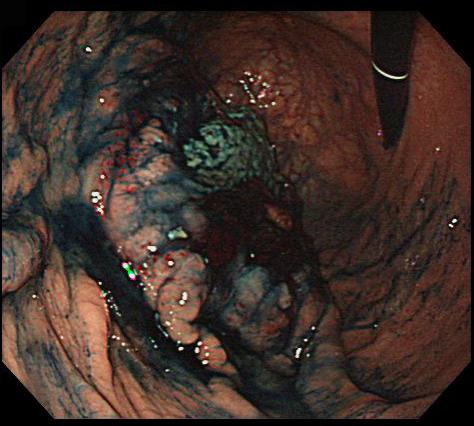

Criteria of Hist.ClassificationMalignant Lymphoma/Malignant lymphoma

LocationStomach/More than one of above

Technique, MethodEndoscopy

Size40 -

Depth of Tumor Invasionserosa (adventitia)